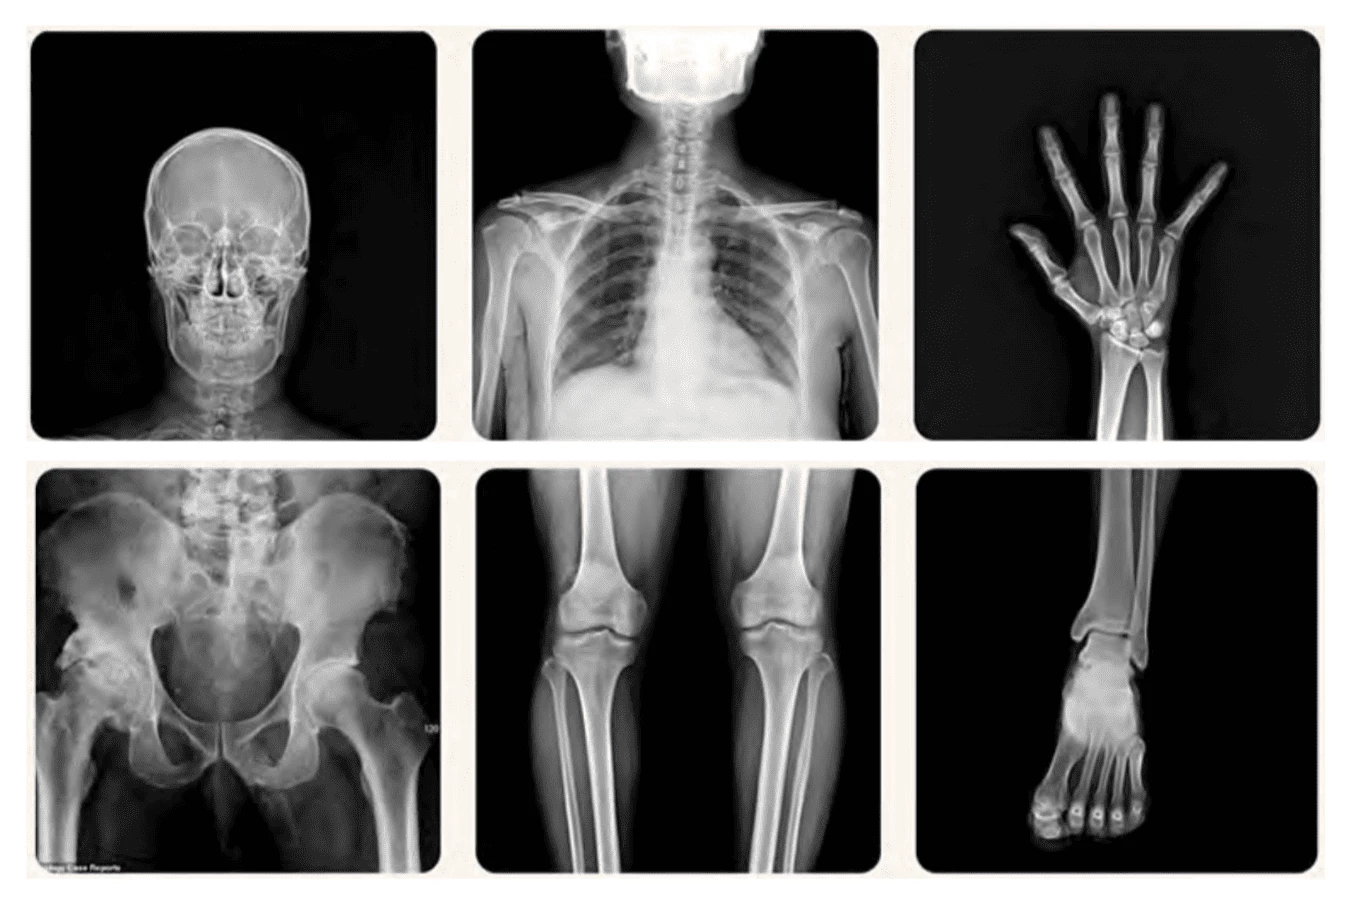

Hệ thống X-quang kỹ thuật số cho hình ảnh rõ nét

Được thiết kế với những tính năng vượt trội, hệ thống X-quang của GE Healthcare mang đến những cải tiến đáng kể khi chụp X-quang kỹ thuật số ngực, xương và cột sống. Hình ảnh thu được có độ rõ nét cao, giúp các bác sĩ chẩn đoán bệnh một cách chính xác và nhanh chóng hơn (trích xuất từ hệ thống X-quang tại Bernard)